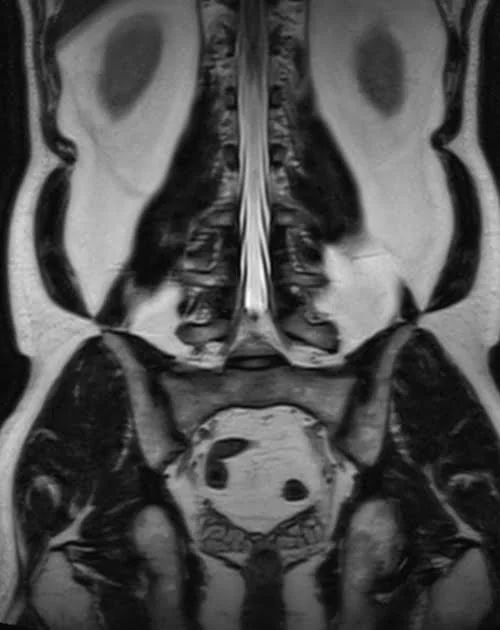

l plexus mri SPACE 3D coronal images